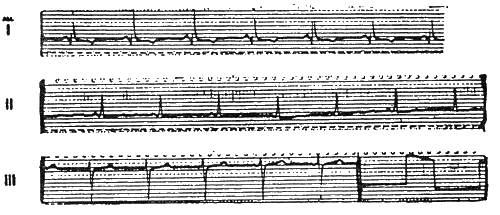

В сентябре и октябре Гитлеру делают рентгенограмму головы, а 24 сентября электрокардиограмму. ЭКГ показывает не только склеротические изменения в коронарных сосудах, но и нарушенную нервную проводимость и гипертрофию левого желудочка сердца. Имел ли место во время описанного приступа инфаркт, с уверенностью утверждать по результатам ЭКГ нельзя. Однако это очень вероятно.

После изучения кардиограммы, проведенного директором Института исследования сердца в Бад-Наухайме профессором Карлом Вебером, которому Морель переслал ЭКГ, врач может порекомендовать и без того придерживающемуся лежачего режима апатичному Гитлеру только одно: еще больше беречь себя.